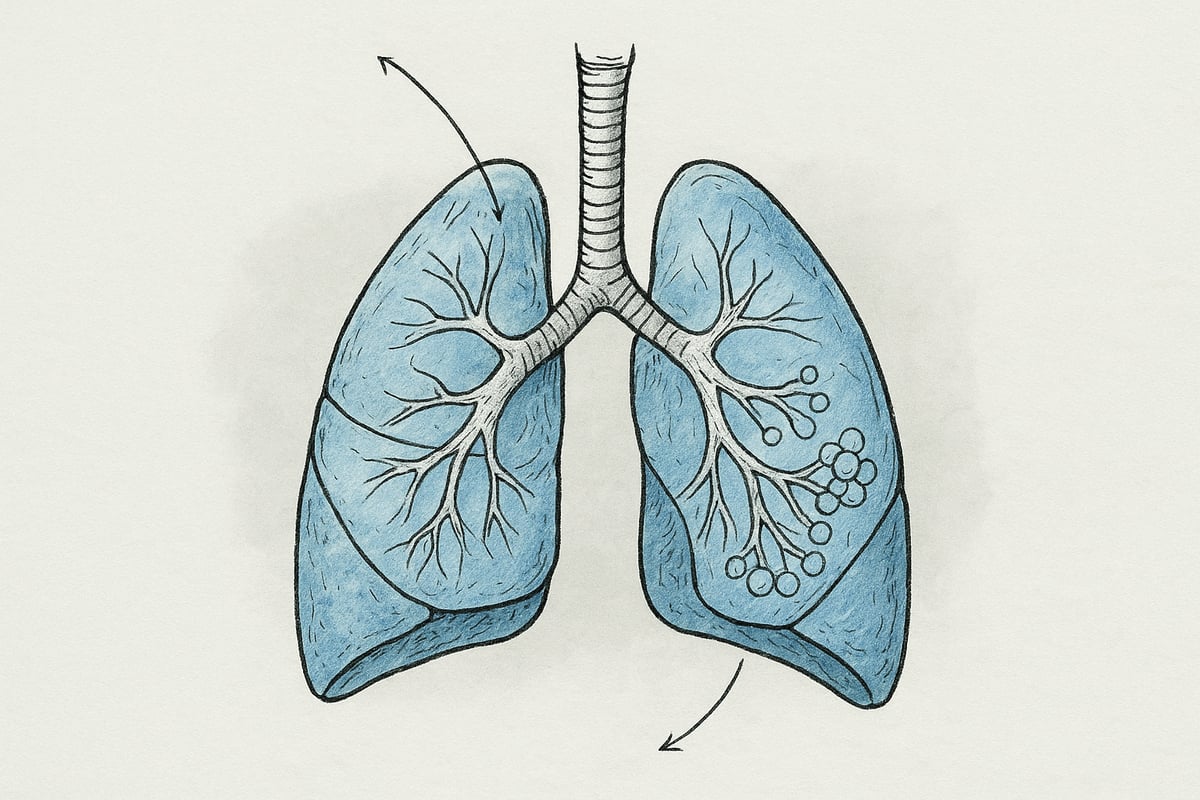

Lungernes placering og struktur

Lungerne befinder sig i brysthulen, beskyttet af ribbenene og adskilt af hjertet. Den højre lunge består af tre lapper, mens den venstre har to lapper for at give plads til hjertet. Dette skaber en forskel i både form og volumen mellem de to sider.

Lungevævet er elastisk, hvilket er afgørende for, sådan fungerer lungerne, da det tillader lungerne at udvide sig og trække sig sammen ved hvert åndedrag. Inde i lungerne forgrener luftrøret sig til bronkier, som deler sig til mindre bronkioler og ender i millioner af alveoler.

Alveolerne er små luftsække, hvor udvekslingen af ilt og kuldioxid finder sted. Samlet set dækker alveolernes overfladeareal omkring 70-100 m2, hvilket svarer til størrelsen på en tennisbane. Dette enorme areal er nødvendigt for at sikre optimal gasudveksling.